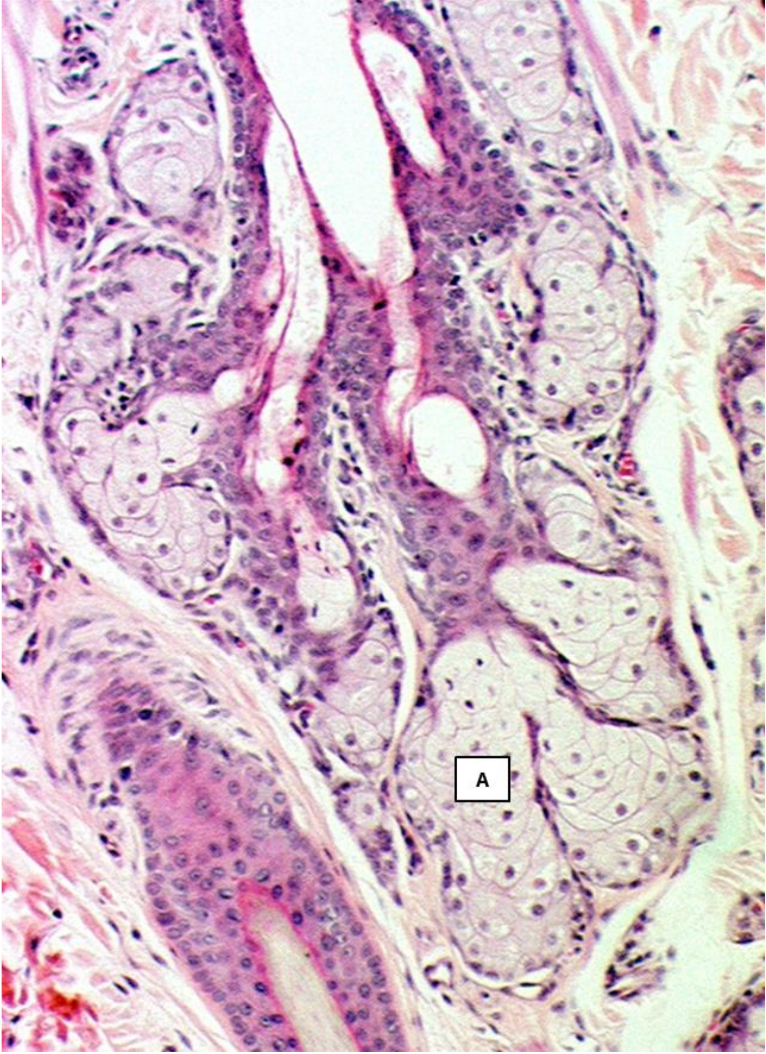

What type of glands are indicated by A?

Sebaceous gland

What type of gland is represented in the picture?

Hepatoid gland